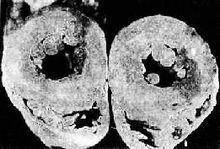

1.重要器官病理形態改變積分 MOFE 顯著高於MOF。低灌注4h,其總積分為MOF 組14 倍,心腎病變積分為MOF 組的22 倍;低灌注8h,各器官病理變化積分分別為MOF 組的2~6 倍,其中肺的損傷尤為嚴重。損壞最重的器官,MOFE組是肺,MOF 組是腎;器官損壞嚴重程度順序,MOFE 組是肺、肝、心、腎、胃腸;MOF 組是腎、肝、心、肺、胃腸。

4.腎臟 在低血流量灌注時,各重要器官中,最早受影響的是腎臟。因老年人最容易腎動脈硬化、腎小管萎縮。所以當腎血流量減少到一定程度時,腎臟微循環內微聚物形成,腎小管上皮壞死,發生腎功能衰竭。臨床表現為少尿或無尿,尿素氮(BUN)>35.7mmol/L(100mg/dl),肌酐(Cr)176μmol/L(2mg/dl)。